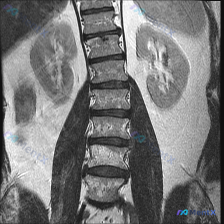

整理到一份有意思的影像资料: - 是一张腰椎+肾脏区域的T2加权冠状位MRI。 - 最初拿到资料时,有人先提了一句「会不会是脊柱侧弯」,但仔细看完影像报告和图像描述后,发现这个方向其实完全站不住脚。 大家先不看后面的完整分析,仅根据目前的描述,大家第一眼觉得: 1. 这份影像是否存在脊柱侧弯? 2....

最近碰到这个很典型的病例,整理了思路分享给大家,其实临床碰到这类情况很容易踩坑。 病例基本信息 患者:23岁男性 主诉:腰痛6个月 现病史:疼痛晨起更严重,体力活动后改善,布洛芬服用后疼痛显著缓解,无大小便失禁、无勃起功能障碍 体格检查:胸部扩张减少、脊柱活动范围减少,双下肢肌力5/5,双侧髌骨反射...